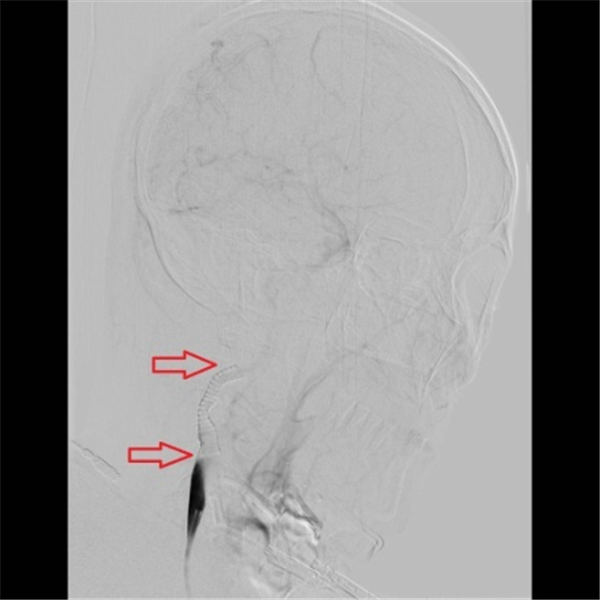

术后再次造影显示,右侧颈内动脉支架位置好,膨胀充分,血流通畅,颅内血管未见异常(上图红色箭头所示)。